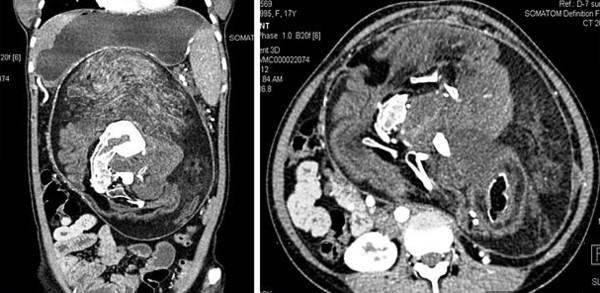

17岁妹肚子诡异隆起 医开刀惊见畸形双胞胎化成肿瘤塞子宫

▲少女肚子异常隆起。 但随着检测越详细,医师发现这个肿瘤的「内容物」相当奇怪,因为里面有各种软组织的器官,甚至有钙质的出现像是骨头、或是脊椎,甚至还参杂着一些毛发。医学报告中提到,基本上该肿瘤为良 ...